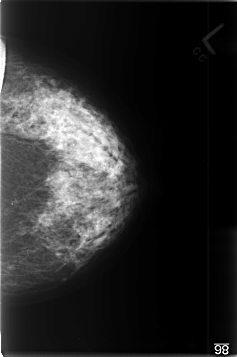

C_0350_1.LEFT_CC

LEFT_CC LINES 4632 PIXELS_PER_LINE 3080 BITS_PER_PIXEL 12 RESOLUTION 50 NON_OVERLAY